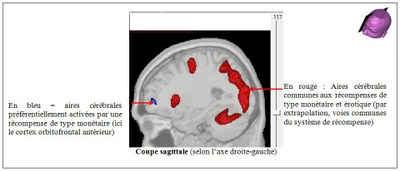

Superposition des 3 images suivantes :

- l’image anatomique IRMsujet13241anatRecompense

- le calque fonctionnel IRMsujet13241fonctionRecompense_ArgentSupErotique

- le calque fonctionnel IRMsujet13241fonctionRecompense_conjonctionargentETerotique.